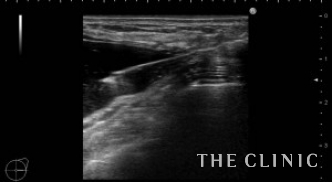

しこりを穿刺し、ヒアルロニダーゼを注入して吸引除去します。

左)吸引後、しこりは消失しました。